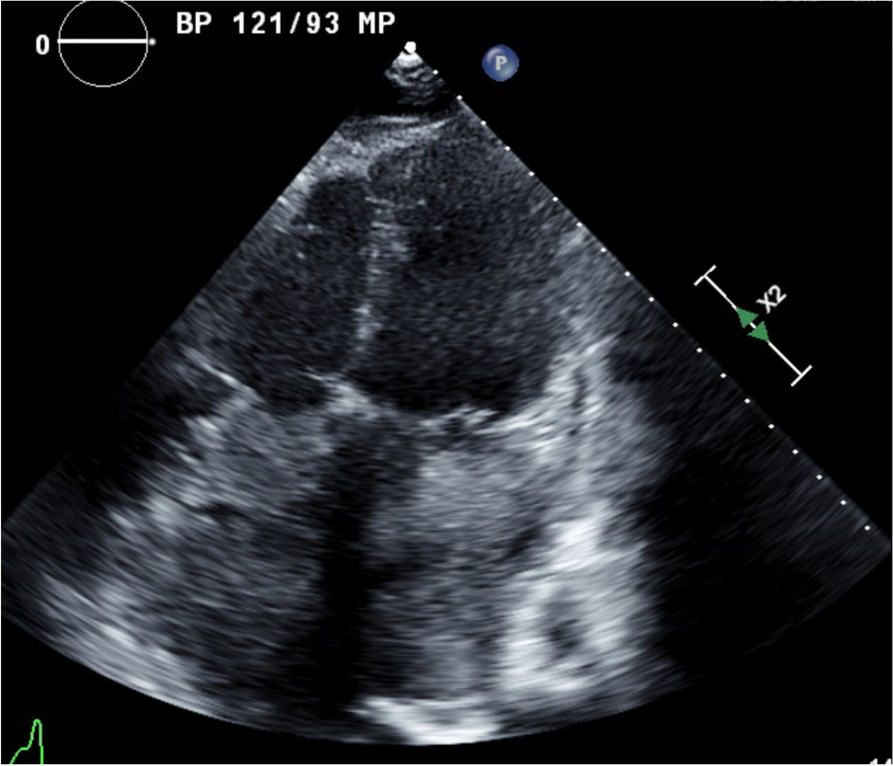

Fig. 1

Echocardiogram with apical four-chamber view showing large atrial mass occupying both left atrium and right atrium, obliterating the interatrial septum